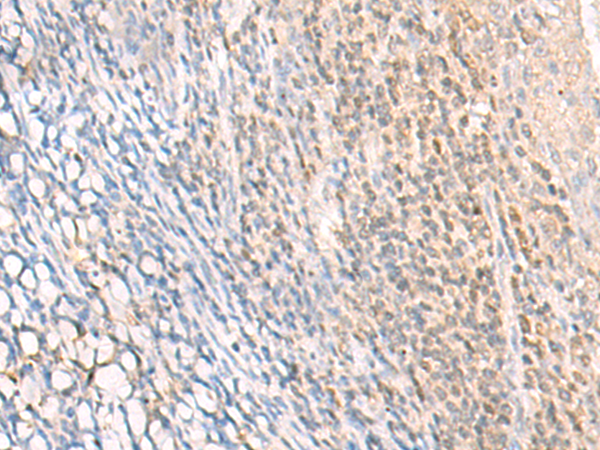

IHC positive control: |

Human cervical cancer and Human tonsil |

IHC Recommend dilution: |

30-150 |